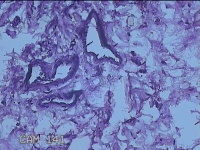

性别

女

年龄

36岁

临床诊断

皮肤良性肿瘤

发现左侧大腿息肉组织2年余,无明显疼痛及不适。

左侧大腿息肉组织

大体所见

灰白粉红色息肉样组织4.3x3.3x0.8cm一块,表面光滑,切开组织呈实性,切面灰白粉红色,质软。

图3